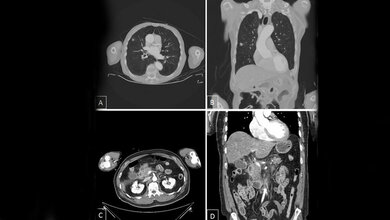

Prof. Dewey: Die CT reduzierte die Notwendigkeit eines Herzkatheters von 100 % auf 14 % in der Gruppe von Patienten, die zuerst eine CT an Stelle des Herzkatheters erhielten. Wenn in der CT-Gruppe ein Herzkatheter durchgeführt wurde, fand sich fünf Mal häufiger eine KHK als in der Gruppe von Patienten, die direkt einen Herzkatheter bekamen. Im langfristigen Verlauf nach 3,3 Jahren gab es keine vermehrten Herzkatheteruntersuchungen und keine Zunahme von Herzkreislaufereignissen bei den Patienten in der CT-Gruppe. Die CT verkürzte außerdem den Aufenthalt der Patienten um 23 Stunden und wird von 79 % der Patienten für zukünftige Untersuchungen bevorzugt. Somit zeigt die BMJ Studie die Eignung der CT zum zuverlässigen und schonenden Ausschluss der KHK bei Patienten mit untypischen Brustschmerzen, die aus klinischen Erwägungen bisher zum Herzkatheter überwiesen wurden.

Marc Dewey, Matthias Rief, Peter Martus et al.: Evaluation of computed tomography in patients with atypical angina or chest pain clinically referred for invasive coronary angiography: randomised controlled trial. BMJ 2016; 355: i5441, DOI: dx.doi.org/10.1136/bmj.i5441 (Published 24 October 2016)